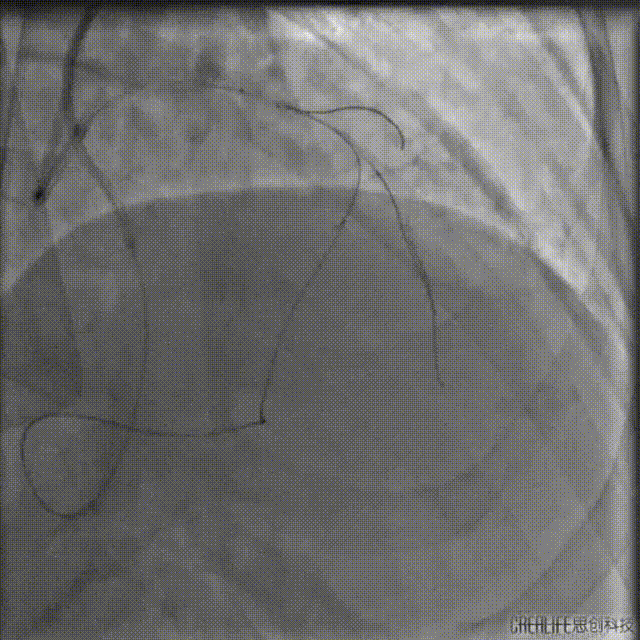

左冠:7Fr EBU3.5;右冠:7Fr AL1.0;Runthrough导丝送至RCA远端,LAD送P200导丝在微导管支撑下进入CTO病变体部。

P200导丝反复调整仍无法突破CTO病变远段,遂走行至D1,通过逆向造影进一步确认。

送入双腔微导管增强支撑,并送入第二根P200导丝继续尝试正向进攻,未能进入LAD中段真腔。

撤出微导管,1.5mm球囊扩张LAD近段后,送入IVUS导管,明确LAD近段导丝是否走行在真腔内,观察LAD在D1分叉处的开口位置,指导CTO导丝的进攻方向。

回撤显示导丝位于真腔,分叉处CTO入口在11-12点处,遂在X线影像中标记入口位置。

重新送入双腔微导管及P200导丝,在CTO入口处尝试进入远端真腔,但反复调整导丝仍未成功。